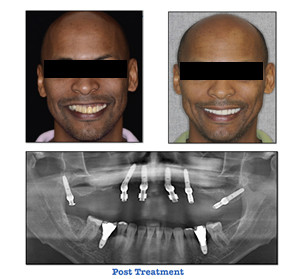

FABRICATION OF CONVERSION PROSTHESIS

Z. Khan BDS1, D. Garazi DMD2, I. Garazi DMD2,T. Balshi DDS, PhD1 1Nova Southeastern University, Post-Graduate Prosthodontics, Fort Lauderdale, FL, 2Nova Southeastern University, Post-Graduate Periodontology, Fort Lauderdale, FL

Immediate Loading of Pterygomaxillary Implants with Fixed Full-arch Fully Milled Prostheses (Avadent) in the Maxilla: : A Case Report

Chief complaint “I am unhappy with my smile, I don’t like the discrepancy in my teeth and gums”.